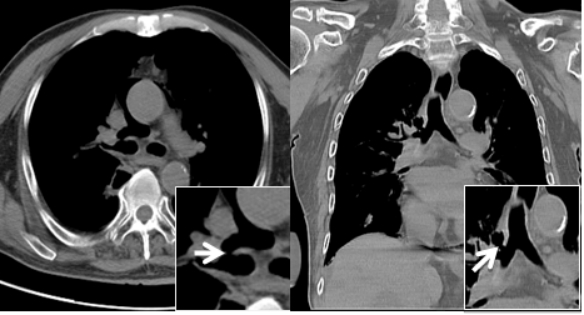

| 图 5 胸部CT(纵隔窗)白色箭头所指处为右主支气管与上叶支气管壁交界处见小缺损,考虑为右支气管破裂 |

1 资料与方法患者男性,70岁,因“胸闷3 d,加重伴呼吸困难1 d”于2019年9月13日入外院。患者3 d前无明显诱因出现胸闷,伴全身乏力,夜间睡眠差(可平卧),初未予重视,1 d前胸闷加重,伴呼吸困难、运动耐量明显下降、大汗淋漓、皮肤湿冷,至外院就诊,查心电图(图 1):交界性逸搏,肢体导联低电压,Ⅰ、Ⅱ、Ⅲ、aVF、V4、V5、V6导联ST段抬高0.15 mV~0.4 mV,aVR、aVL、V1导联ST段压低0.05 mV~0.2 mV,aVL、V1导联T波倒置;心肌酶:CKMB 27.1 U/L,NT-proBNP 3 298 pg/mL。外院考虑不排除急性心肌梗死导致的心源性休克,经口气管插管接呼吸机辅助通气后为进一步诊治转入本院。患者家属否认患者有外科手术、外伤、气胸及哮喘发作史,起病以来无畏寒、高热,大、小便正常,既往1年余前因“反复咳嗽伴咳血丝痰”在外院诊断为右肺门鳞癌,合并高血压病、2型糖尿病,经依托泊苷+顺铂化疗,具体剂量不详。2019-09-07复查胸部CT提示右肺病灶较前缩小。体格检查:体温35ºC,血压86/43 mmHg,心率53次/min,呼吸15次/min(经口气管插管呼吸机辅助呼吸),神志昏迷,双侧颈静脉怒张,气管居中,桶状胸,胸廓对称,双肺呼吸动度对称,叩诊呈清音,听诊呼吸音清,双肺未闻及干湿性啰音,心前区无隆起,叩诊心界消失,心音低弱遥远,桡动脉、股动脉搏动可触及。入院后复查心电图(图 2):心房颤动,肢体导联及胸导联低电压,各导联ST-T改变较前相似,未见明显动态演变。血常规:白细胞1.27×109/L,中性粒细胞1.15×109/L,血红蛋白98 g/L,降钙素原43.01 ng/mL,超敏肌钙蛋白Ⅰ 0.048 ng/mL。急诊冠脉造影(图 3):左前降支近段轻度狭窄,中段心肌桥,收缩期重度狭窄,左回旋支远段中度狭窄,右冠中段重度狭窄,TIMI血流均为3级。患者超敏肌钙蛋白I未见明显升高,冠脉血流通畅,排除急性心肌梗死引起的ST段抬高。心脏彩超:气体干扰较大,仅能从剑突下观察,心包腔内未见积液。胸片(图 4):纵隔内可见条状透亮带,心影周围可见一弧形透亮带,考虑心包积气、纵隔气肿。入院诊断为“①心包积气、②纵隔气肿、③右肺鳞癌”,经剑突下途径行心包穿刺置管术+闭式引流术,术后液封瓶内见气体逸出,患者血压较前逐渐上升。完善胸部CT(图 5):右侧肺门增大,右主支气管与上叶支气管壁交界处见小缺损,考虑支气管破裂,心包、纵隔、胸腔及腹腔积气。纤维支气管镜(图 6)检查:可见右主支气管距隆突约1 cm处见破损,破损处周围组织呈白色,不排除癌组织浸润可能。病因考虑为右肺门鳞癌浸润右主支气管,穿孔后经纵隔与心包腔形成瘘道,引起心包积气。经过上述治疗后患者血流动力学稳定。

该例患者主要临床症状为胸闷伴有呼吸困难,体格检查时患者存在血流动力学不稳定及意识障碍,结合心电图、心肌酶结果,考虑急性心肌梗死导致心源性休克的可能,行急诊冠脉造影发现患者冠脉血流通畅,排除急性心肌梗死,同时在冠脉造影过程中发现患者心影周围存在弧形透亮带,转入ICU后行胸片检查证实心包积气的诊断。心包积气产生的原因主要为医源性操作(如心包穿刺术、胸腔穿刺术、射频消融术及埋入式起搏器植入术等)、心包炎、心包与邻近含气器官之间的瘘管形成以及外伤,其中正压通气亦是原因之一[9-12]。正压通气可迅速增加心包积气容积及加快其增长速度,从而加重心包填塞。该患者入外院后行经口气管插管接有创呼吸机辅助呼吸,本院胸部CT与支气管镜检查可见右主支气管破口,破损处周围组织呈白色,不排除癌组织浸润可能,考虑为右肺门鳞癌浸润右主支气管,穿孔后经瘘道与纵隔及心包腔相连,引起心包积气。